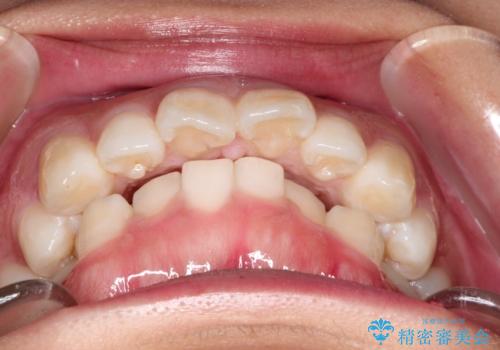

- 出っ歯を主訴に来院されました。

下の歯並びに対して、上の歯が全体的に前方に位置している状態でした。

上の歯の前から4番目の歯を2本抜歯して、そのスペースに前歯を移動させて、前歯を引っ込める計画としました。